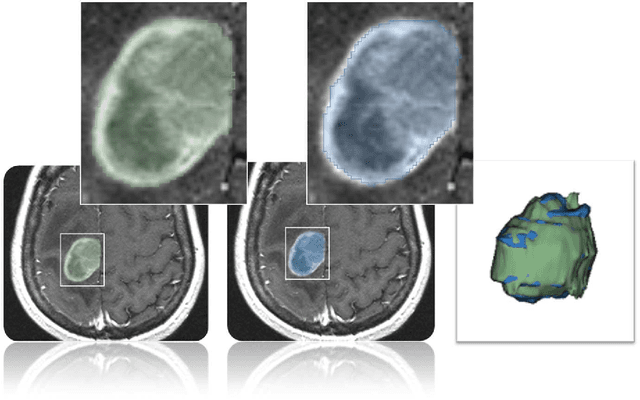

Abstract:In this study, we present pituitary adenoma volumetry using the free and open source medical image computing platform for biomedical research: (3D) Slicer. Volumetric changes in cerebral pathologies like pituitary adenomas are a critical factor in treatment decisions by physicians and in general the volume is acquired manually. Therefore, manual slice-by-slice segmentations in magnetic resonance imaging (MRI) data, which have been obtained at regular intervals, are performed. In contrast to this manual time consuming slice-by-slice segmentation process Slicer is an alternative which can be significantly faster and less user intensive. In this contribution, we compare pure manual segmentations of ten pituitary adenomas with semi-automatic segmentations under Slicer. Thus, physicians drew the boundaries completely manually on a slice-by-slice basis and performed a Slicer-enhanced segmentation using the competitive region-growing based module of Slicer named GrowCut. Results showed that the time and user effort required for GrowCut-based segmentations were on average about thirty percent less than the pure manual segmentations. Furthermore, we calculated the Dice Similarity Coefficient (DSC) between the manual and the Slicer-based segmentations to proof that the two are comparable yielding an average DSC of 81.97\pm3.39%.